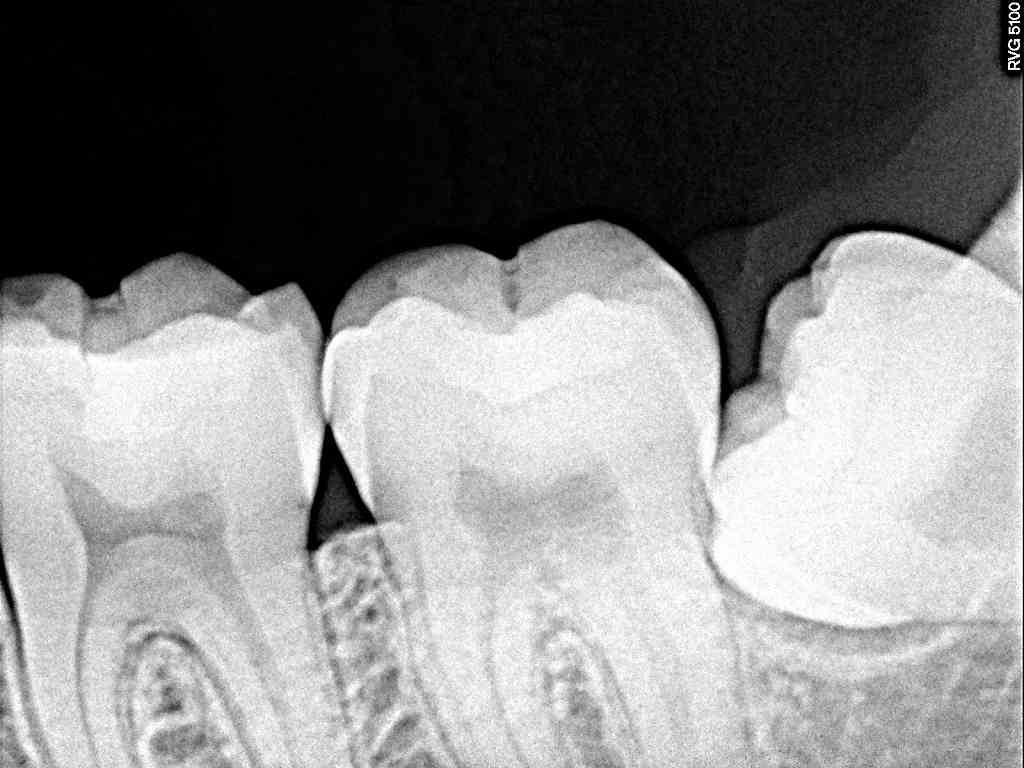

左下水平埋伏歯の抜歯 難抜歯の部類となります|お知らせ |広島市安佐南区の歯科医院 左下水平埋伏歯の抜歯 難抜歯の部類となります トップ お知らせ・ブログ お知らせ 左下水平埋伏歯の抜歯 難抜歯の部類となります 左下水平埋伏歯の抜歯 難抜歯の部類となります ここに親知らずが埋伏しています 歯茎が腫れています 何度か腫れては良くなるとのこと デンタルレントゲンになります パノラマになります 少し最小限で切開を加えています 歯冠部を分割しています 縫合して終了となります このように抜歯できました Web診療予約 初めての方へ 選ばれ続ける理由 院内設備について 歯が痛いしみる一般歯科 歯がぐらぐらする歯周病 健康な歯を保ちたい予防歯科 子供の虫歯予防をしたい小児歯科 銀歯をセラミックに審美歯科 白い歯を目指しませんか?ホワイトニング 矯正専門医がいるので安心矯正歯科 抜けた歯を補いたいインプラント・入れ歯 医院案内 スタッフ紹介 メリィハウス歯科クリニックオフィシャルホームページ ラベンダー歯科クリニックオフィシャルホームページ お知らせ・ブログ ホーム 診療科目 一般歯科 歯周病治療 予防治療 小児歯科 審美治療 ホワイトニング 矯正歯科 入れ歯・インプラント マウスピース矯正 初めての方へ 院長・スタッフ 設備紹介 医院案内・アクセス メニューを閉じる